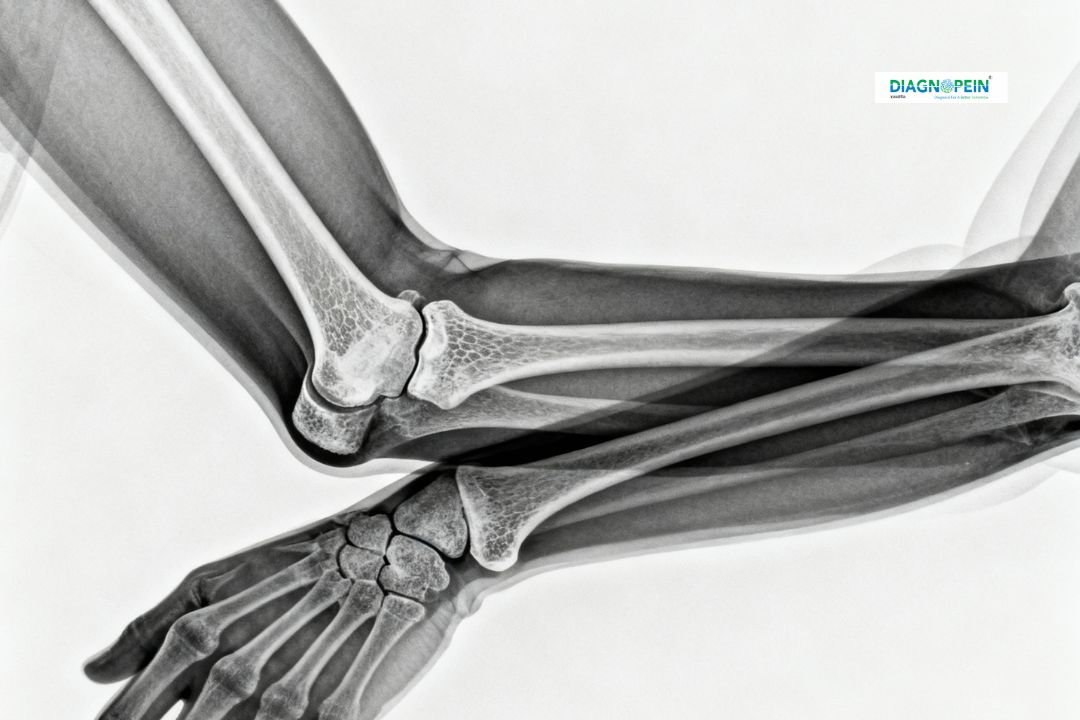

At Diagnopein in Karad, we provide precise X-Ray Forearm AP/LAT imaging for patients who have sustained fractures, bone injuries, or need evaluation for bone alignment and joint conditions. This diagnostic imaging test captures detailed front (AP – Anteroposterior) and side (LAT – Lateral) views of the forearm bones, including the radius and ulna. By offering high-quality, digital X-ray imaging, our radiology center ensures quick and accurate results to assist your doctor in diagnosis and treatment planning.

An X-Ray Forearm AP/LAT is essential for detecting bone fractures, dislocations, and deformities. It also helps assess bone healing after surgery or immobilization in a cast. This test provides vital information about:

1. Fractures or bone cracks in the radius or ulna

2. Bone deformities or abnormal angulation

3. Joint alignment issues (wrist or elbow)

4. Detection of infections, cysts, or bone tumors

5. Evaluation of post-surgical healing or implant placement